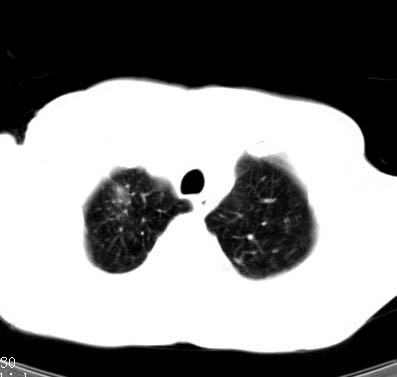

标题: CT14027:男性病人 71岁 咳嗽咳痰数周. [打印本页]

标题: CT14027:男性病人 71岁 咳嗽咳痰数周.

男性病人 71岁 咳嗽咳痰数周.诊断结核应该有保障吧!

支持双上肺继发性肺结核。

tb应无悬念